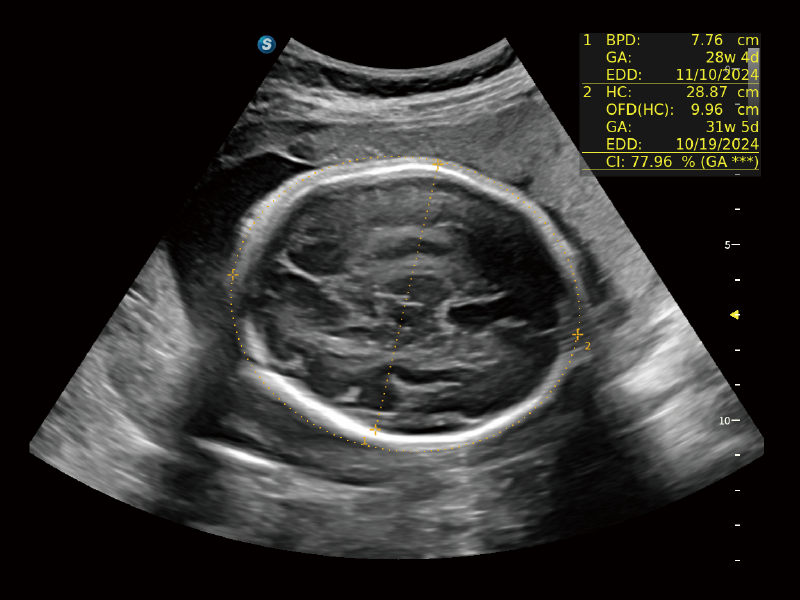

作为开立医疗全新打造的超高端旗舰超声产品,从探头抬起唤醒开启扫查到多维探头发射接收,通过先进的场成像发射、自适应聚合重建等技术,基于RF Data原始射频数据在图像生成、高端功能等方面实现突破,为妇产科、儿科提供全方位临床解决方案。